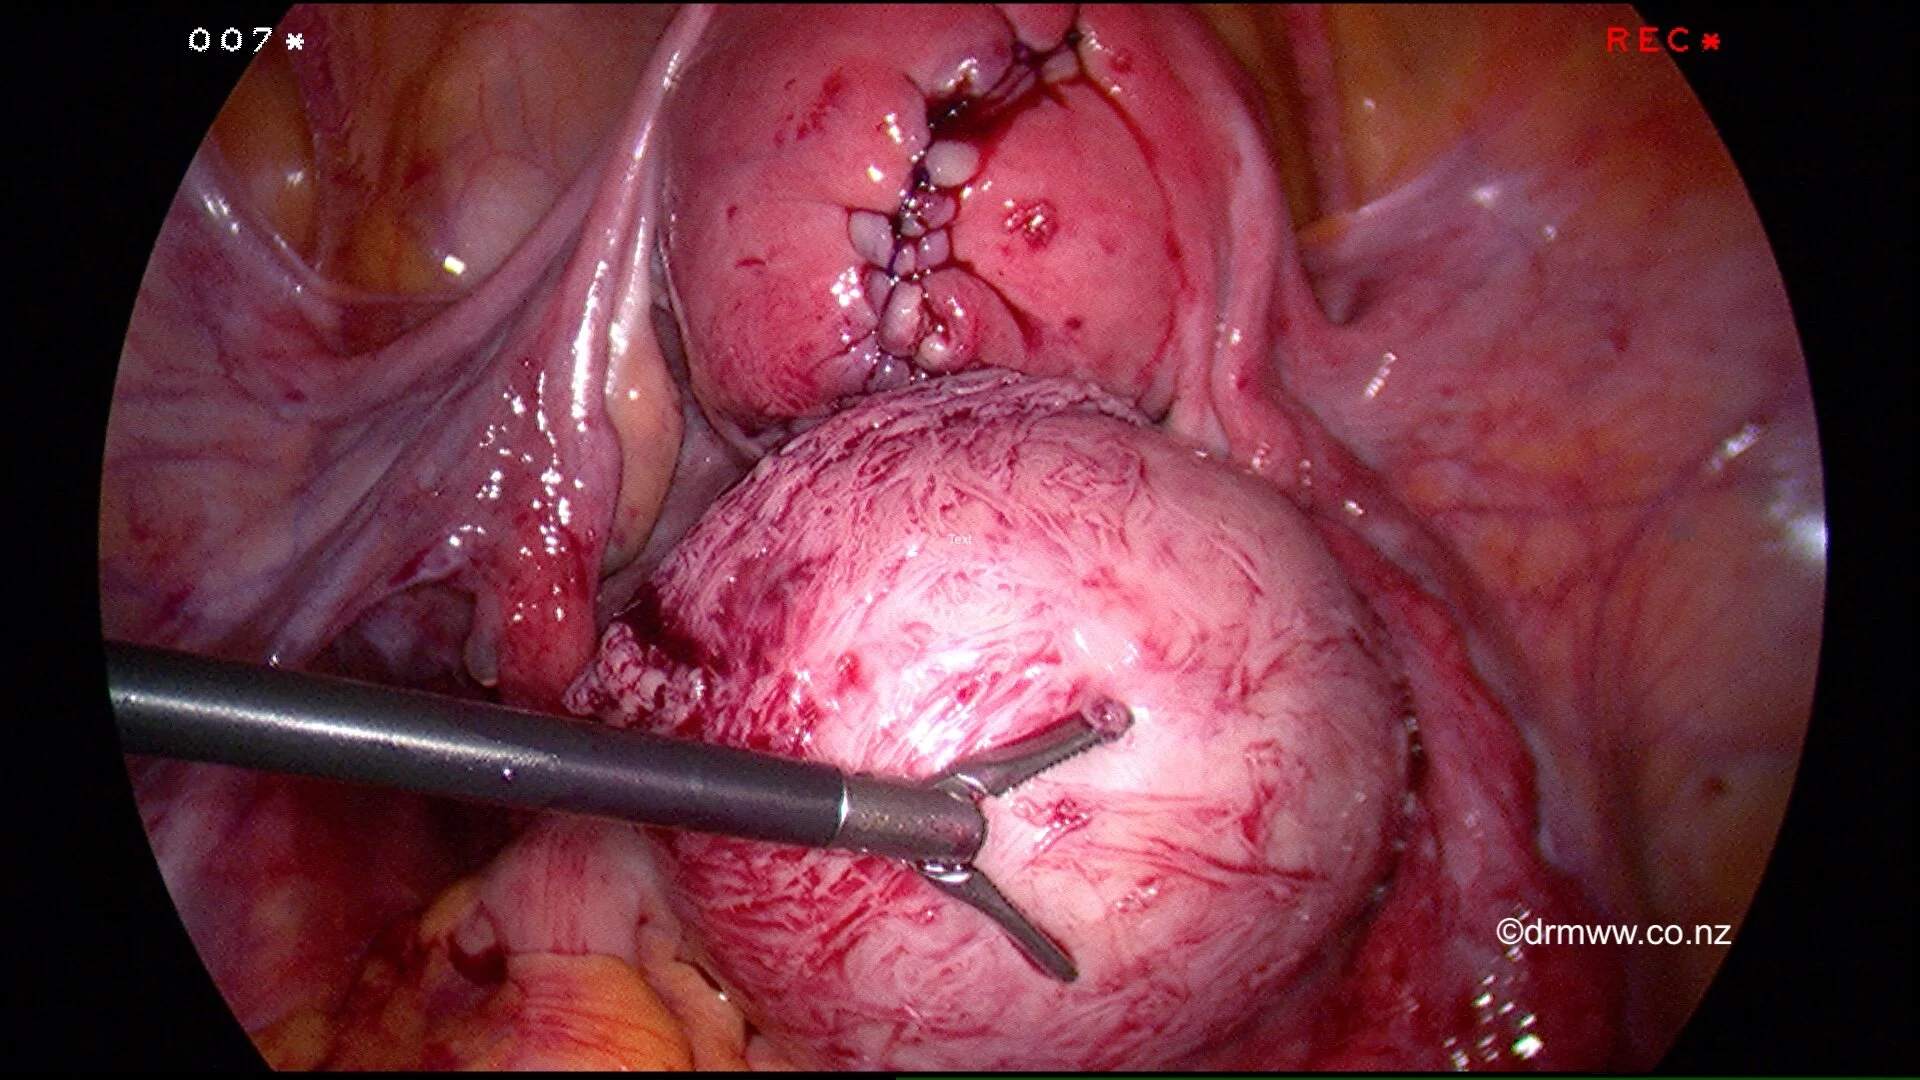

A repaired uterus and the fibroid that was removed laparoscopically.